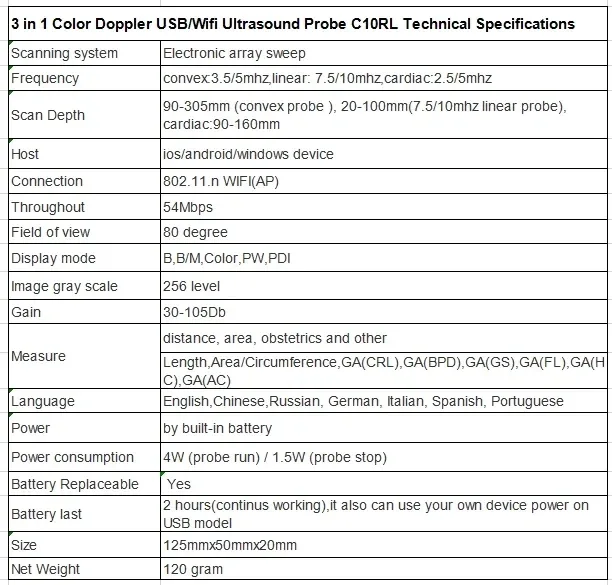

Small Full Digital Portable Ultrasound Equipment with Android/IOS Windows

Convex Probe Parameters

-Scanning system: array sweep

-Frequency: 3.5MHz

-Probe element: 80

-Depth: 90-200mm

-Host:

IOS: IPAD mini/IPAD air/IPHONE etc.

Android: Smartphone/pad, Samsung, HTC, Sony, Huawei, LG etc.

Windows: windows 10 system

-Connection: 802.11.g WIFI(AP)

-Throughout: 54Mbps

-Field of view: 80 degree

-Display mode: B,BM

-Image gray scale: 256 level

-Gain:30-105Db

-Measure: distance, area, obstetrics and other

GA(CRL),GA(BPD),GA(GS),GA(FL),GA(HC),GA(AC)

-Language: English, Russian, Italian, Spanish, Chinese, Portuguese

-Power: by built-in battery

-Power consumption: 10W (probe run) /2W (probe stop)

-Battery last: 3 hours

-Footprint: 156mmx60mmx24mm

-Weight: 308 g